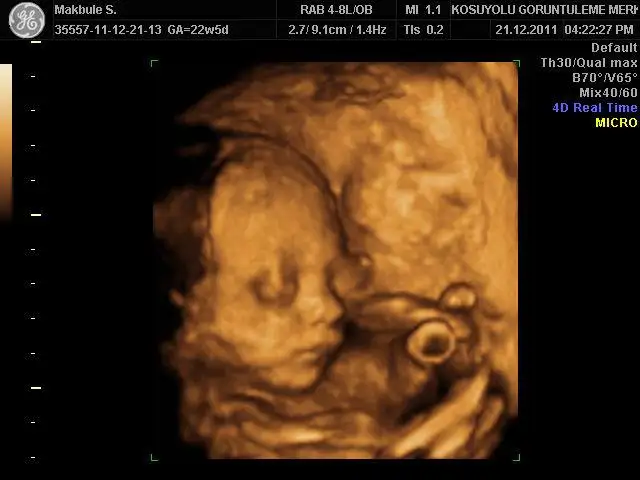

Ayrintili Ultrason Goruntusu 21 Haftalik 21 Week Youtube